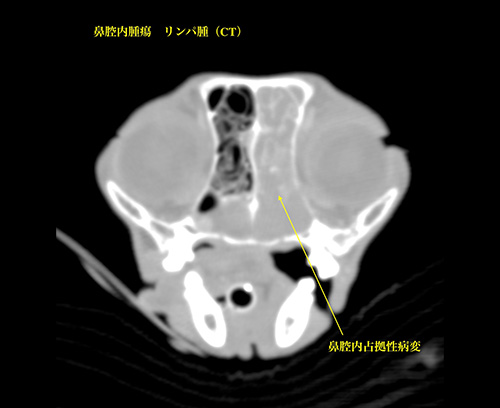

鼻腔内腫瘍(リンパ腫)